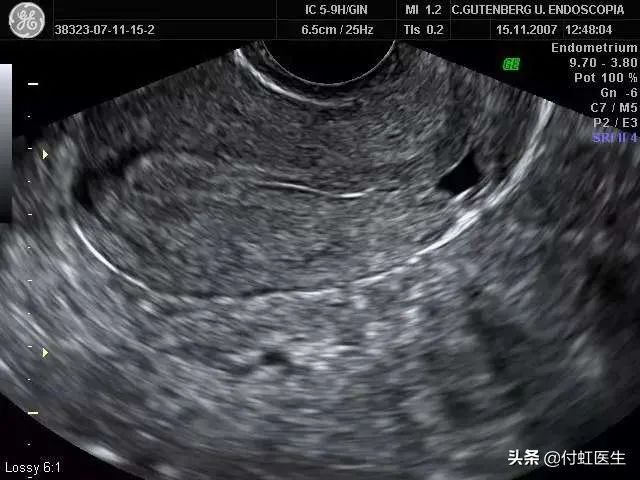

分析晴女士经期延长的原因就是她曾经做的“剖宫产”,B超提示子宫剖宫产瘢痕处钙化,但是分析同时瘢痕处恢复不佳,或者存在小憩室,B超尚未发现。

5.做什么检查可以诊断?

6.CSD 的诊断应结合患者的剖宫产史、月经延长、月经淋漓不尽等症状以及辅助检查。